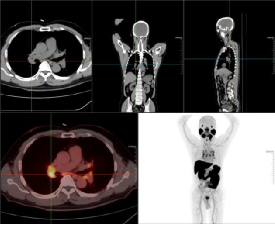

老年男性,前列腺增生病史,发现左侧颈部肿块多年,排尿困难,分叉5年,血精,怀疑前列腺肿瘤。PET/CT图如下。第一排为CT图,第二排分别为融合图、MIP图。

左侧颈部、颌下腺下后方、纵隔内(2R、4R、4L、5、6、7、8)及双侧肺门多发肿大淋巴结影,大者位于左侧颈部,最大截面约28.5mmX20.0mm,放射性摄取增高,SUVmax6.80,左侧颌下腺受压移位,考虑淋巴结转移灶,建议穿刺病理检查。

前列腺体积增大,并向前上凸入膀胱,腺体密度欠均匀,最大横径约55.3mm,前后径约42.5mm,腺体内点、条状高密度影,放射性摄取局限性增高,腺体中央部和外周部为著,摄取增高范围约38.1mmX27.3mm,SUVmax7.09,前列腺包膜局部略毛糙,考虑前列腺Ca,肿瘤突破包膜不除外。